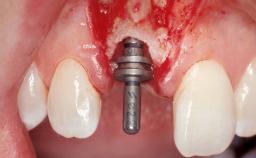

Late Placement of an Implant in a Maxillary Left Central Incisor Site

A 36-year-old female patient was referred for the replacement of the upper left central incisor (tooth 21), which had fractured. Although the tooth had been asymptomatic for many years, the crown began to loosen, at which time she presented to her dentist for an assessment. Teeth 21 and 22 had both been endodontically treated many years previously. She was a healthy individual and a non-smoker.

| Bone Volume | Deficient horizontally, requiring prior grafting |